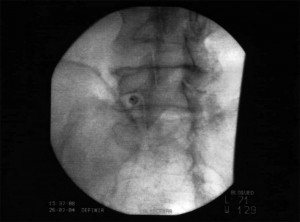

TÉCNICA

Con el  paciente en decúbito prono se realiza una proyección con el arco de fluoroscopia en Ap hasta localizar los cuerpos vertebrales de L2, L3 y L4. Posteriormente y con el arco de fluoroscopia en posición oblicua muy forzada (15-20º) hacia el lado a tratar, hasta que el cuerpo vertebral cubra la apófisis transversa del lado afectado, en ocasiones la apófisis transversa es demasiado grande y obliga a realizar una proyección oblícua extrema que dificulta el bloqueo, en estos casos lo más adecuado es realizar una proyección sagital caudocranea y elevar la apófisis transversa para poder acceder al punto diana. El punto diana es la interserción entre el borde inferior de la apófisis transversa con el cuerpo vertebral, donde se introduce la aguja curva, a través de un abocath n º16, avanzando hasta sobrepasar el borde anterior cuerpo vertebral observándolo con una proyección lateral qie posterormente se comprueba  con contraste. Se comprueba con el arco de fluoroscopia en en posición AP .La punta de la aguja debe estar medial al borde lateral del cuerpo vertebral. Los bloqueos pueden ser; bloqueo diagnostico terapéutico: ropivacaina 0.5% o bupivacaina 0.5% o lidocaína 2%, 3-5ml, bloqueo neurolítico: fenol 6-10% (3-5ml) o alcohol 50-100% (3-5ml) a varios niveles. En caso de radiofrecuencia; estimulación sensorial: (50Hz) a 1v puede producir dolor profundo en el abdomen y molestias vagas en la región lumbar. Si aparecen parestesias en la ingle recolocar la aguja (nervio genitofemoral). Estimulación motora (2Hz) a 3v no deben existir contracciones motoras en el miembro inferior. Una vez realizada la estimulación se inyecta 1-2ml de lidocaína al 2% y se realiza una lesión del 80º durante 90 segundos.